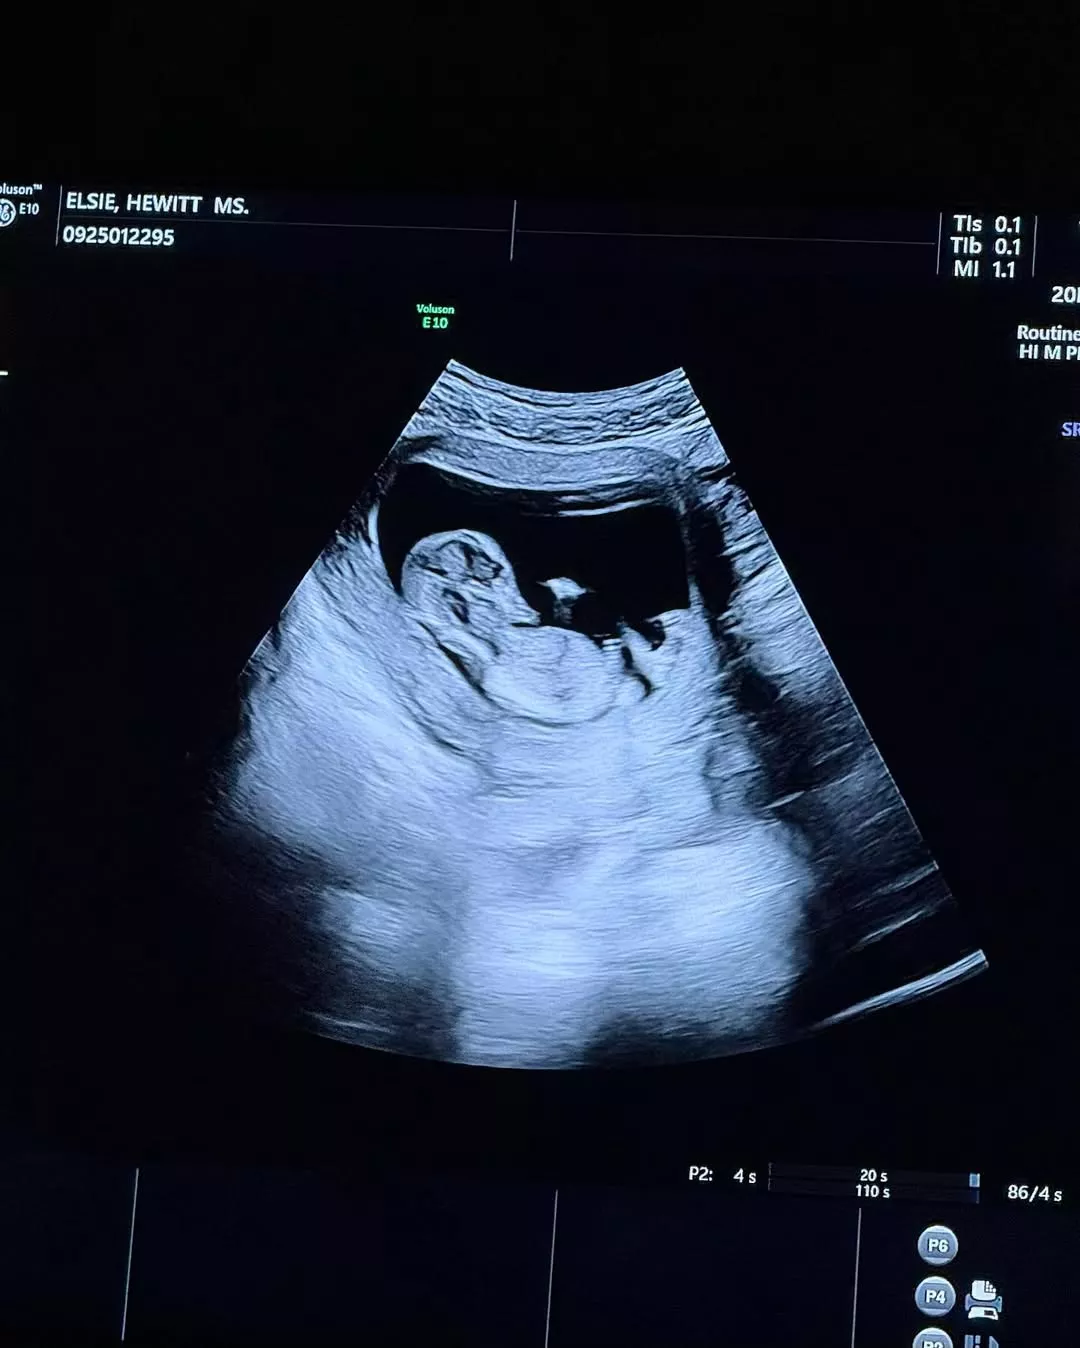

Pete Davidson and Elsie Hewitt have announced their new journey in life, as they are expecting their first child. The couple, who started dating in March 2025, left their fans shocked with the news. Elsie shared the news on her Instagram account, posting sweet photos with Pete and an ultrasound picture. A source close to the couple revealed that they both are super excited to start a family, but have been keeping the news private. It stated: